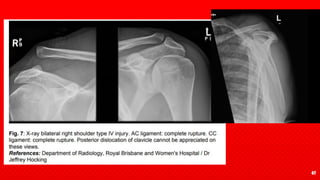

Type IV: Both the AC and CC ligaments

are completely ruptured. X-ray will

show the clavicle displaced

posteriorly into the trapezius

muscle. Lateral radiograph

demonstrates the clavicle

overriding the acromion, which is

suggestive of a posterior

dislocation

confirming a type IV injury is with the axial and/or scapular view on X-ray